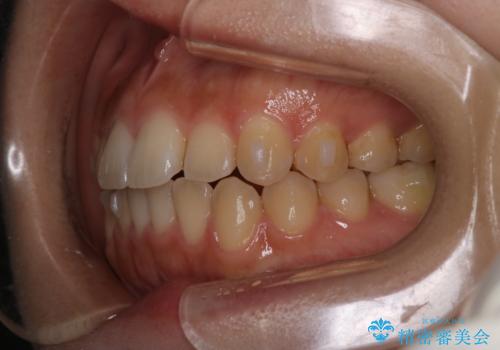

- 前歯の叢生を主訴に来院されました。非抜歯でインビザラインで治療をしました。

叢生はIPRをし、並べました。この患者様はオープンバイトだったため歯を並べる過程でかみ合わせも治しました。